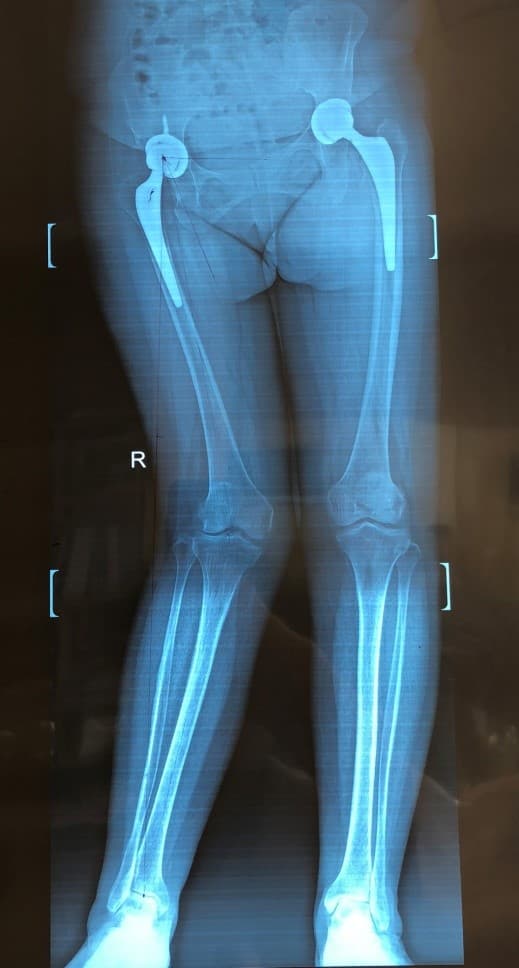

Түнхний төрөлхийн дутуу хөгжил, мултралын улмаас хоёр түнхний үеийг солих мэс засал хийгдсэн эмчлүүлэгчид хийгдсэн саруй хөл засах мэс заслын өмнөх болон дараах рентген зураг